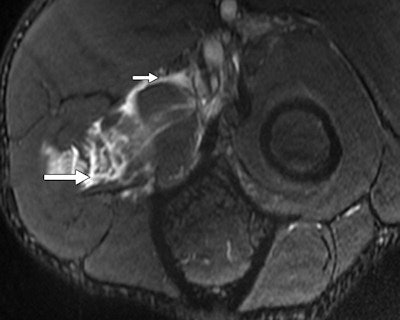

"Elbow injuries in Olympic sports have not been reported previously," noted lead author Dr. Sarath Bethapudi, from the department of musculoskeletal radiology at Leeds Teaching Hospitals National Health Service (NHS) Trust in the U.K. "Most of the injuries resulted from valgus strain with hyperextension of the elbow and usually presented as injuries to the medial joint supporting structures. Combinations of medial and lateral ligaments were seen in combat and power sports with high-energy acute trauma. Such injuries also resulted in tears to secondary stabilizers of the medial joint, including the common flexor tendons and medial muscular compartments" (AJR, September 2013, Vol. 201:3, pp. 535-539).

Of the 28 elbows scanned for acute sports injuries, 15 had high-grade ligament injuries, and 12 of these ligament injuries occurred in contact sports and weightlifting. The remaining three injuries were seen in throwing athletes, two of whom were javelin throwers and one of whom was a volleyball player.

"Tears of the common flexor and extensor tendons occurred in combination with ligamentous injuries. This occurs because common flexors and extensors act as secondary stabilizers of the elbow joint and are injured when the primary stabilizers fail. Once again, these injuries occurred primarily in combat sports, weightlifting, and overhead-throwing athletes," stated Bethapudi, who was responsible for data collection and analysis at the 2012 Olympics and has received funding from GE Healthcare, a sponsor at the games.

Significant ligament and tendon injuries to the elbow can occur often in nonthrowing athletes, and most of the elbow injuries seen in these athletes were isolated high-grade ulnar collateral ligament (UCL) injuries, although combinations of medial and lateral ligament injuries can occur, the authors concluded. Ulnar attachment tears were the next most common injuries, followed by midsubstance tears of the UCL. This trend differs from the existing literature, which suggests that midsubstance tears are the most common type of UCL injuries, they wrote.